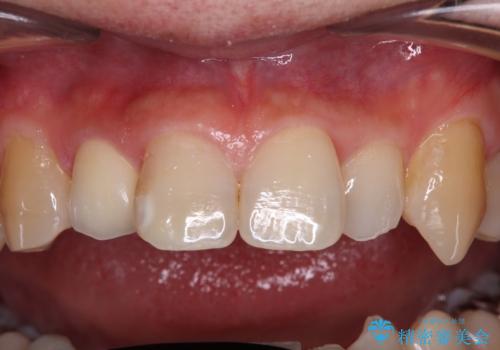

内側に倒れているため、下顎と強く干渉することが懸念されましたが、無理のない咬み合わせで、形態も左右対称に近い状態で仕上げることができました。